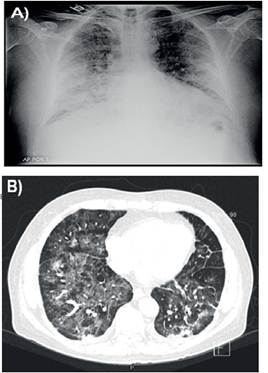

Se realiza tanto radiografía de tórax así como tomografía computada de tórax (TC-Tx) donde se observan infiltrados pulmonares con patrón en vidrio esmerilado alternado con áreas de menor atenuación con patrón en empedrado, zonas de engrosamiento septal de aspecto reticular con predominio en postero-basales, afectación panlobar y presencia de pequeñas atelectasias bibasales (Ver Figura 1 A y B).